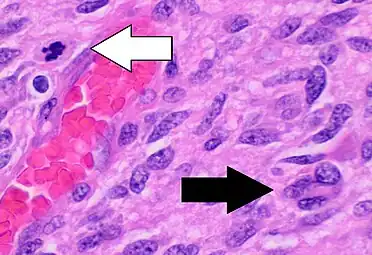

Histopathology of glioblastoma, showing high grade astrocytoma features of marked nuclear pleomorphism, multiple mitoses (one at white arrow) and multinucleated cells (one at black arrow), with cells having a patternless arrangement in a pink fibrillary background on H&E stain.